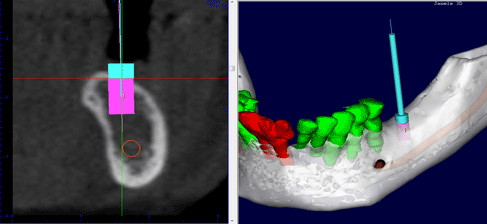

O exame de tomografia cone beam é liberado, em média, em até 3 dias úteis, dependendo da necessidade de urgência. São fornecidas imagens dos cortes tomográfico da região selecionada e as reconstruções 3D que podem ser impressas em papel fotográfico colorido ou filme radiográfico, de acordo com a preferência do profissional. Além dos cortes impressos e o laudo, todo o exame é gravado em um CD contendo o material impresso e um software interativo. Este software possibilita que o dentista planeje virtualmente a colocação de implantes, realize medidas de remanescentes ósseos e localize estruturas anatômicas, ou seja, fornece uma oportunidade única de estudo ao profissional, favorecendo o entendimento e,conseqüente sucesso do tratamento.